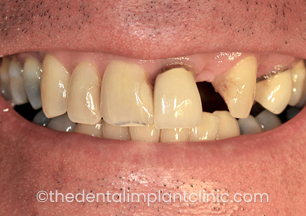

The pre-operative photo with existing implants, missing teeth and old crowns

The pre-operative photo with missing teeth and stained crown margin